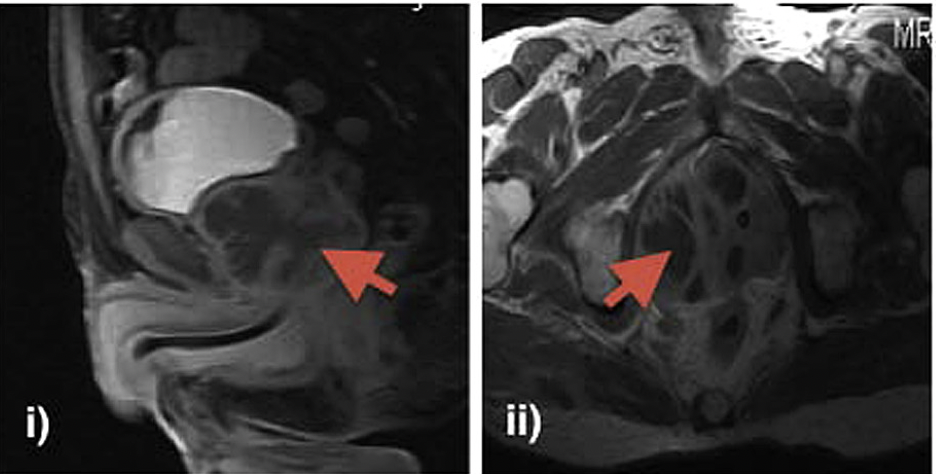

Transurethral Deroofing of Prostate Abscess

A prostatic abscess is an uncommon urological emergency, but it is a serious infection of the prostate with a high mortality rate unless properly treated. Patients with diabetes mellitus, renal insufficiency, and immune suppression are particularly at risk. Urethral catheterisation, lower urinary tract instrumentation, and a prostate biopsy are among the possible predisposing factors. Once liquefaction and abscess formation are diagnosed, several approaches have been described for drainage. Open perineal drainage, transurethral deroofing, transrectal needle aspiration, or tube drainage, and percutaneous drainage are the main therapeutic options. #abscess #turp #prostate